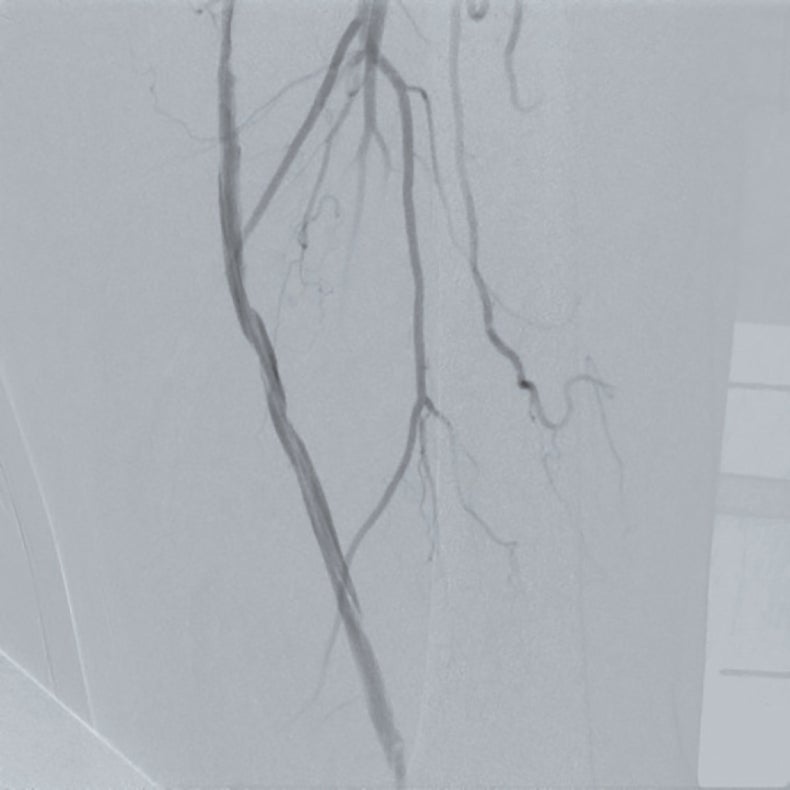

前拡張後の造影で温存したいコラテ部分に解離が認められ(図2)、また、IVUSでヘルシーランディングが可能な位置を確認したところ、遠位部のコラテ(図1矢印②)を温存してヘルシーランディングができることを確認できた。さらにIVUSで血管径を確認し、同等サイズのバイアバーン® ステントグラフトを留置した。バイアバーン® ステントグラフトが展開し始めた後、展開ラインをゆっくり連続した動作で引くようにするとバイアバーン® ステントグラフトの位置がずれることなく留置することが可能であった。その後、バイアバーン® ステントグラフト全長を同径のバルーンで高圧後拡張してIVUSでバイアバーン® ステントグラフトが充分拡張されていることを確認し、手技を終了した。(図3)

治療後は翌日から左下肢は暖かくなり、間歇性跛行もなくなっている。その後2年経過しているが、経過は良好である。

PSVR:術後6か月 1.94 → 術後12か月 0.58 → 術後24か月 0.78

ABI値:左/術前0.68 → 術後1.00 → 術後12か月 1.16 → 術後24か月0.85